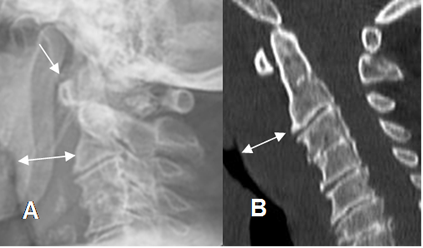

Fig 196. Fractura de Jefferson.

A: Rx lateral y B: TAC reconstrucción sagital. Rectificación cervical, con aumento del espacio retrofaringeo.

El arco anterior de C1 está descendido, en relación con el borde superior de la odontoides, aunque se conserva el espacio normal.